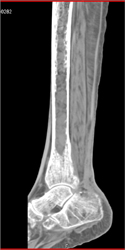

Myeloma